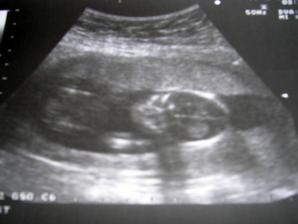

18.září jsme byli na našem 1.IVF... a 8.den od ET se mi "zjevily" nádherné // 🙂... přeju si,aby se všechno vyvíjelo dobře... 29.9 11.den po ET mi pro zhoršení OHSS provedli punkci Douglasova prostoru a odsáli 2 litry žlutého ascitu ☹ Nicméně se mi ulevilo 🙂 HCG ten den 259... 6.10 kontrola HCG - 2950 (18.den od ET)... 10.10 UTZ - čekáme DVOJČÁTKA 🙂 🙂 🙂... 17.10 krvácení a následná hospitalizace, UTZ - dvojčátkům bijí srdíčka, 20.10 HCG - 56000, 25.10 propuštění z nemocnice... 31.10 poslední kontrola v CARu, dvojčátka mají 2 a 2,1 cm... 11.11 UTZ - dvojčátka mají 3 cm... 24.11 UTZ - dvojčátka mají 9 cm (ale moc se mi to měření nezdá, ve čtvrtek na screeningu se ukáže pravda, čeká nás 3D 🙂) 27.11 screening I.trimestru - miminka jsou zdravá, od hlavičky po prdelku mají 7 cm... 19.12 3D - miminko "A" je chlapeček, "béčko" chce zůstat zatím v utajení 🙂 tak snad příště 🙂... 8.1 3D - miminko "B" je holčička 🙂 19.1 echokardiografie - obě srdíčka jsou zdravá 🙂 20.1 screening II.trimestru - vše OK, miminka mají 360 a 364 gramů 🙂 26.1 UTZ - chlapečkovi se ztratil pindík a najednou čekáme 2 holčičky 🙂) Doufám, že už je to definitivní 🙂) 19.2 UTZ 3D4 - holčičky potvrzeny!!! 🙂 mají každá téměř 800 gramů! 🙂 20.3 UTZ - holčičky mají 1700 a 1800 gramů! 8.4 UTZ - holky mají neuvěřitelné váhy 2415 a 2600 gramů! 11.5 nástup do nemocnice... 11.května ve 20,03 se nám akutním císařským řezem narodila Eliška (2970/48) a o minutu později Nelinka (3200/50).Jsme nejšťastnější rodiče na světě! 🙂